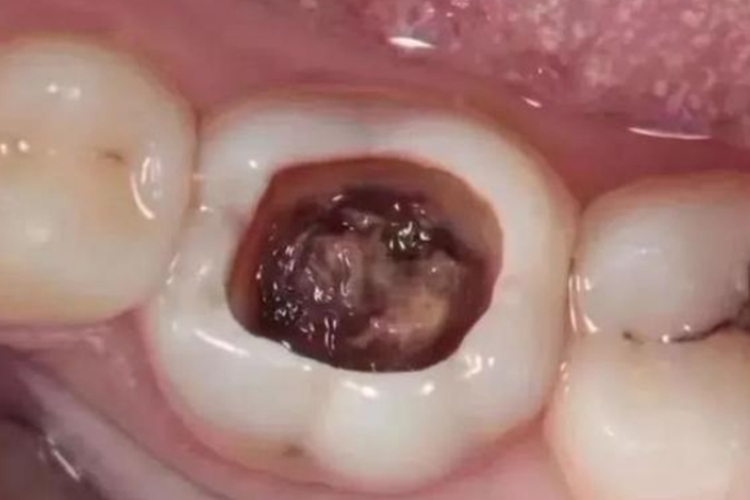

深龋的龋洞深大,达到牙本质深层,临床上表现为颜色改变,龋损部位牙本质呈黄褐或深褐色;形态改变,龋洞形成,牙体缺损明显;质地改变,病变牙本质质地较软。当食物嵌塞入龋洞中或患牙遇冷、热、酸、甜、化学刺激时可出现疼痛,去除刺激后症状立即消失。

根据不同的病情,可采取不同的方法来治疗深龋。首先需去除受损部分的牙齿,防止牙齿被进一步破坏。一般在清除已破损部分后,采用汞合金、合成树脂、陶瓷等填充物填充牙齿,若情况严重还可能需要进行根管治疗或拔除患牙。同时注意避免食用酸性、过冷过热等食物。